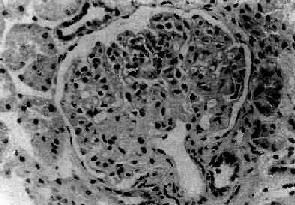

图12-12 新月体性肾小球肾炎

肾球囊壁层上皮细胞增生,其间有单核巨噬细胞浸润形成新月体,肾球囊腔被阻塞